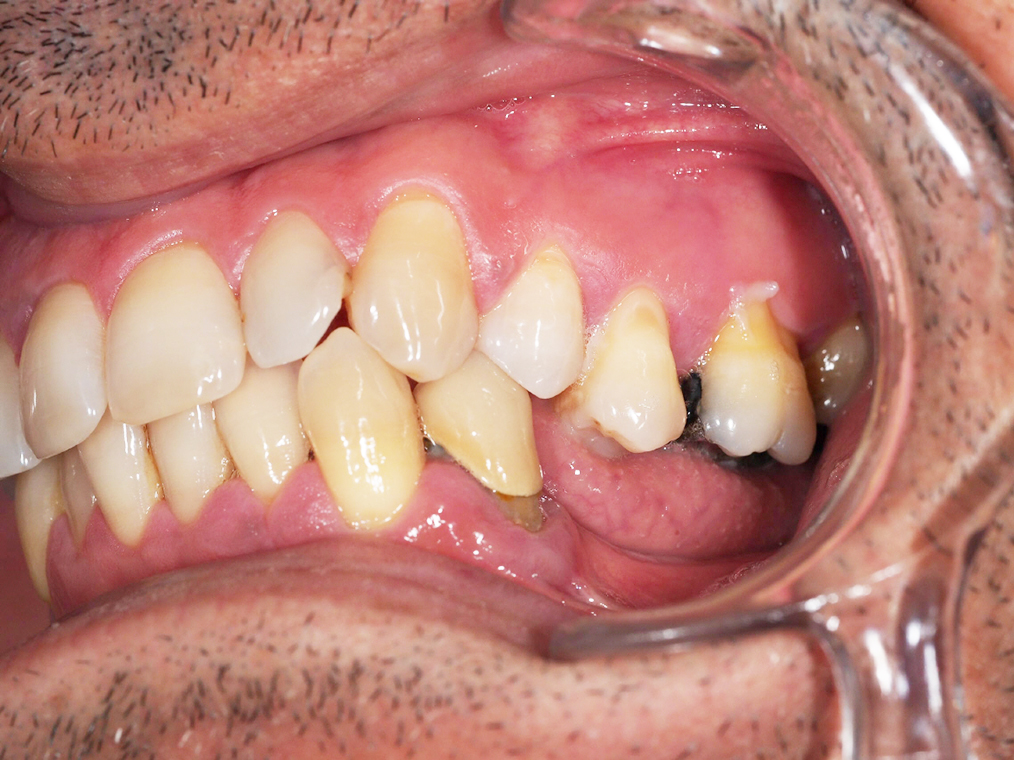

Arcade maxillaire avant traitement orthodontique, séquelles de maladie parodontale